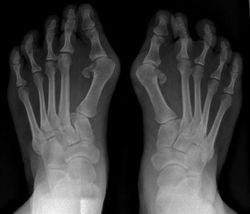

STORETÅEN

Skæv/Indadbøjet Storetå

Hos nogle bøjer storetåen ind mod 2. tåen. Dette medfører ofte en knyst på siden af foden. Det er en tilstand, som tit giver problemer i form af hård hud og ligtorne på knysten, samt en nedgroet negl på storetåen.

Årsag: Forskellige fejlstillinger i fødderne samt forkert fodtøj: Hos nogle mennesker opstår tilstanden lettere end hos andre.Indadbøjet storetå er en tilstand, som ofte hænger sammen med nedsunken forfod.

Behandling: Fodterapeuten kan behandle den hårde hud, ligtornene og neglen samt fremstille aflastninger, så tåen kommer ud på plads - hvis den er mobil. Ved en mobil indadbøjet storetå ses ofte gode resultater med hyppige og vedvarende fodøvelser. Det er ofte en god idé, at kombinere disse behandlinger med indlæg, der kan aflaste årsagerne til fejlstillingen.

Hvis knysten giver meget store gener, kan den opereres.

Behandlingerne er dog kun effektive, hvis der samtidig ses kritisk på det benyttede fodtøj. Fodterapeuten kan vejlede i fodøvelser, der får tåens muskler til at arbejde effektivt igen.